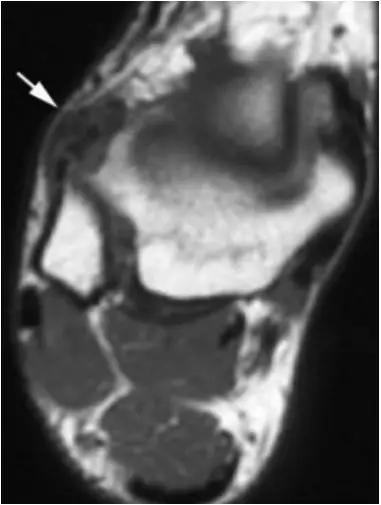

6.后踝撞击综合症:

- 骨性撞击多见,例如距骨后三角骨损伤,距骨或跟骨后突过度增生。软组织撞击表现为后胫腓韧带下部分、横韧带、后踝间韧带的撕裂或肥厚增生。

- 需与跟距后关节骨关节病鉴别。

- 影像学表现为距骨后三角骨的存在或损伤以及距骨后突骨赘形成,导致踝关节跖屈受限,可伴随拇长屈肌肌腱鞘炎症及邻近滑膜不同程度的炎性增生 。

正常后踝韧带;MRI 冠状位T2-FLAIR示踝间后韧带(长箭)